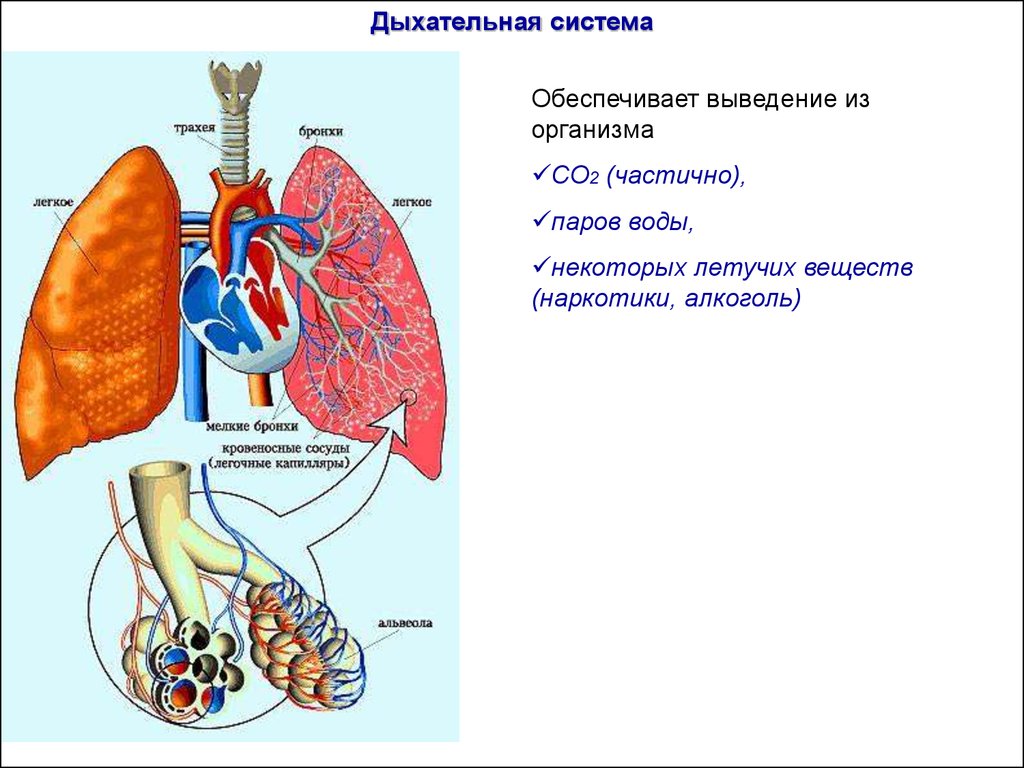

Роль легких в метаболических процессах